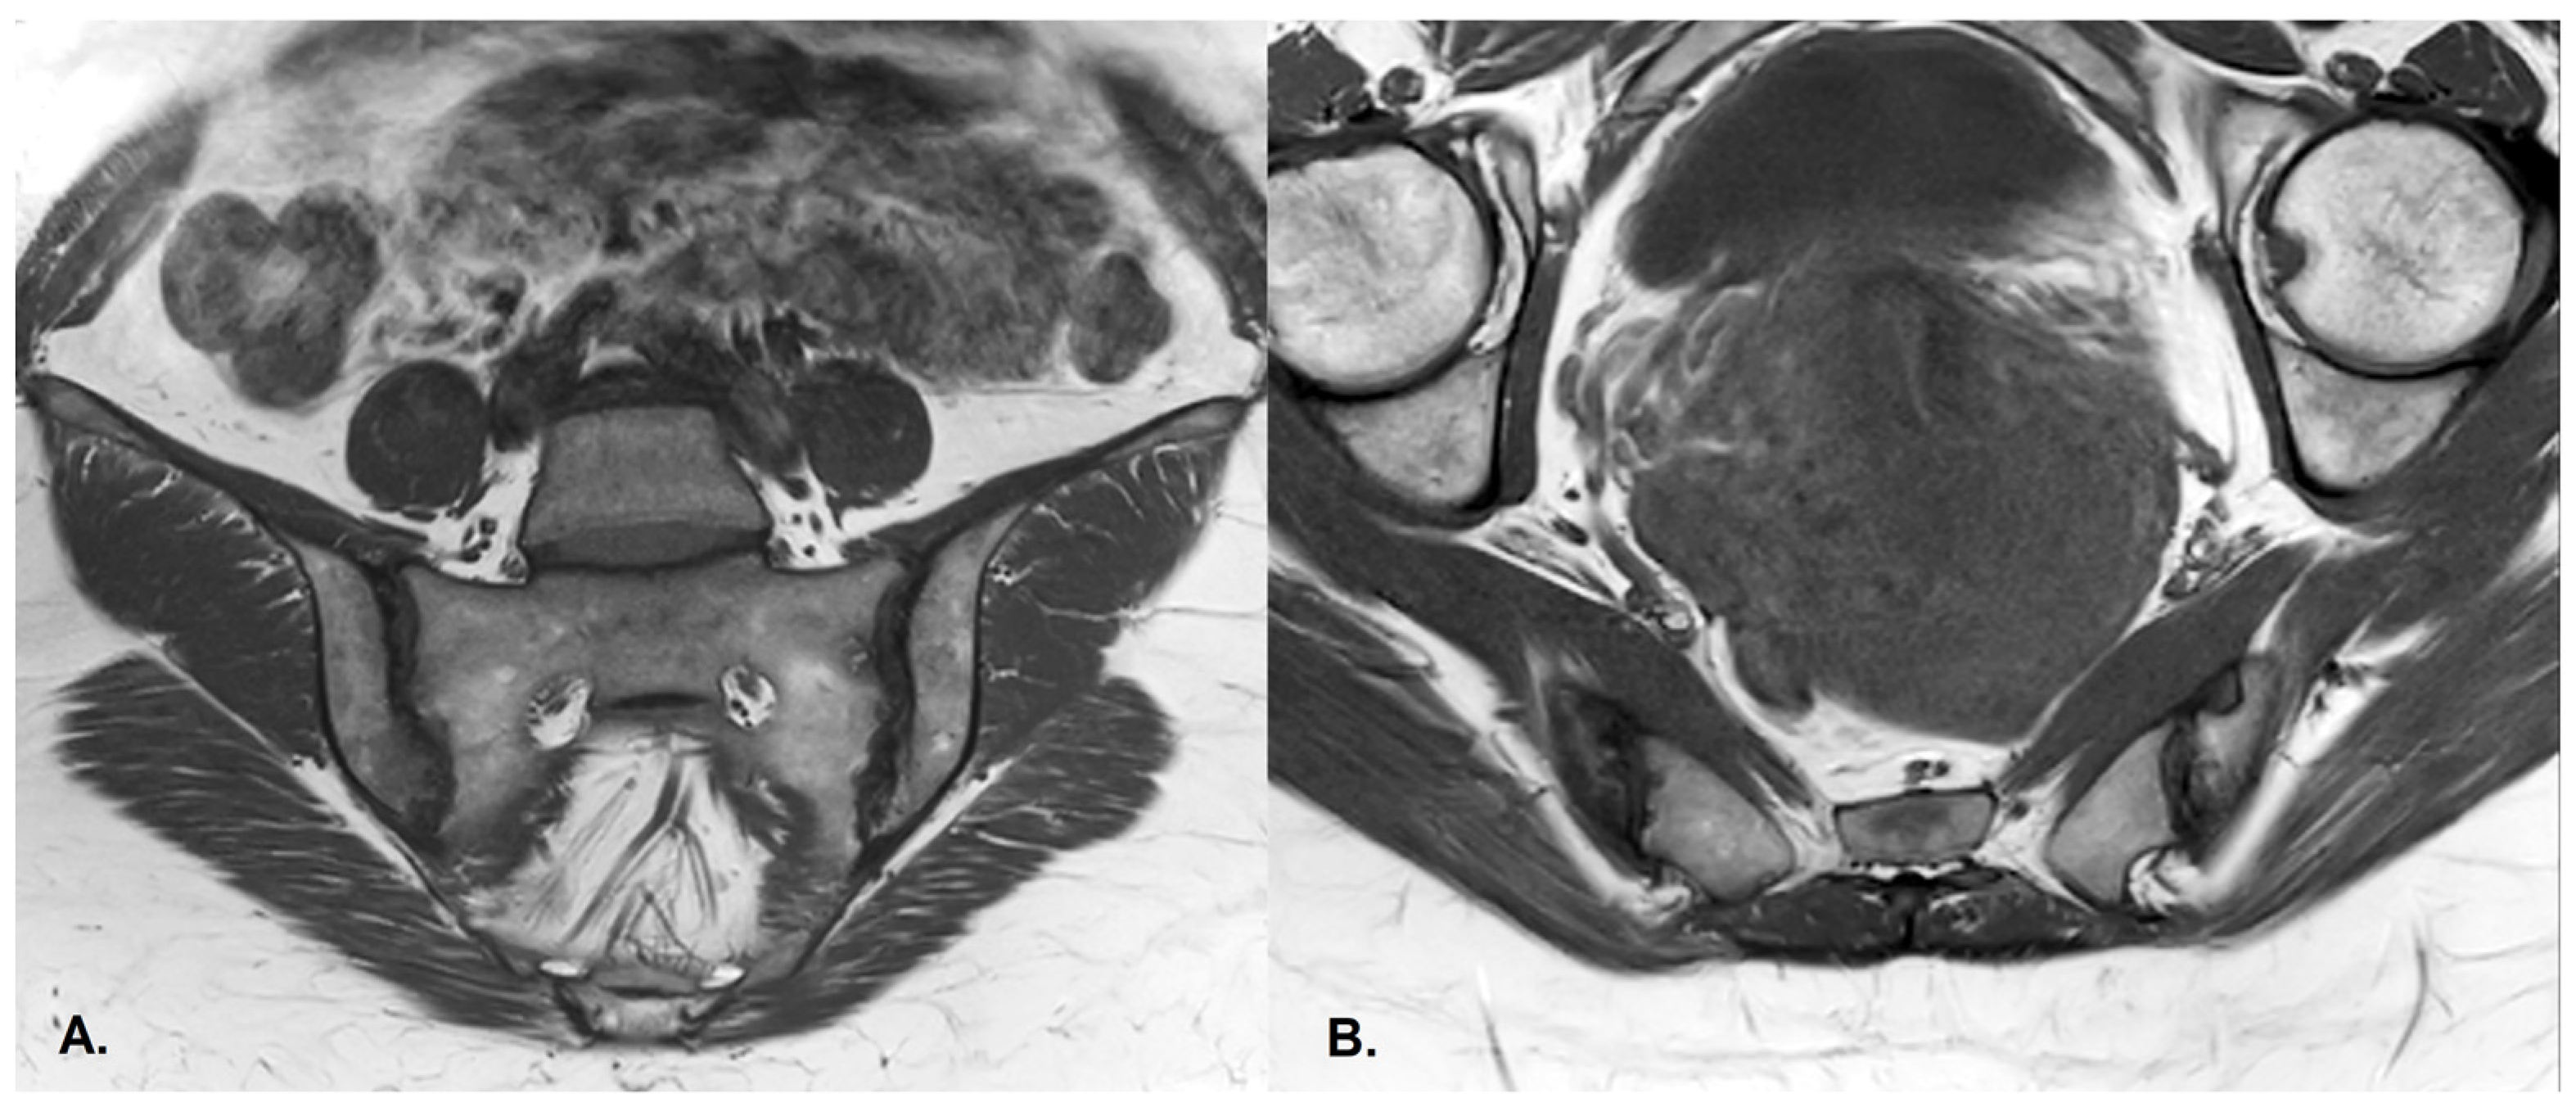

- BME is evident in low signal T1w, hyper signal T2w, STIR images and +C T1w Fat-Sat, similar to blood vessels and spinal fluid; the signal intensity is directly proportional to the inflammation activity. It is usually located periarticular to or on the subchondral bone surfaces and it is an indicator of disease activity (Figure 4) [65].

- Erosions–initially focal, later they will converge and will have a pseudo-enlargement aspect of the sacroiliac joint. In T1w images there is a loss of cortical bone signal (normally hypointense) and bone marrow fat (normally hyperintense).

- Sclerosis—better visualized on an X-ray or CT scan; a subchondral or periarticular area with a low signal compared to normal bone marrow on T1, T1FS (SPIR), and STIR sequences (Figure 5).Slight: <25% of the subcortical bone area.Moderate: 25% to <50% of the subcortical bone area.Severe: >50% of the subcortical bone area [29].

- Ankylosis [65]Partial: Partial osseous bridging across the joint space.Total: Fusion of the joint facets [29].